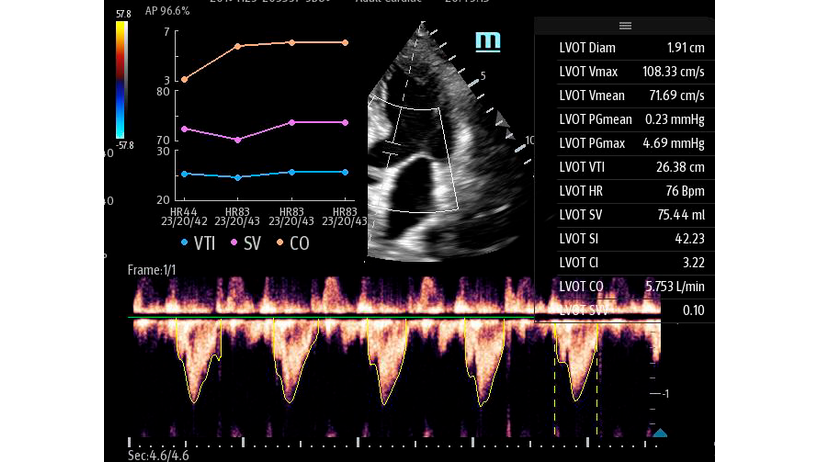

Чтобы использовать уравнение, нужно получить поток выносящего тракта левого желудочка в PW допплере — это достаточно кропотливая работа. В ультразвуковых системах Mindray Resona i9 эта задача решается автоматической оценкой потока выносящего тракта – Smart VTI.

Доктору остается получить 5-ти камерное сечение сердца и нажать одну кнопку на сенсорном экране. Прибор сам выберет расположение контрольного объема, получит спектрограмму и обведет спектр с расчётом всех показателей. Быстро и эффективно.